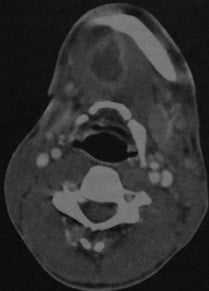

КТ с контрастированием: абсцесс дна полости рта справа с распространением под нижнюю челюсть. Абсцесс примыкает с правой стороны к телу нижней челюсти, определяется как образование со сниженной плотностью в центре, окруженное усиленной стенкой. Поднижнечелюстная железа смещена кзади (стенка абсцесса интактна, инфильтрация в данном случае отсутствует).